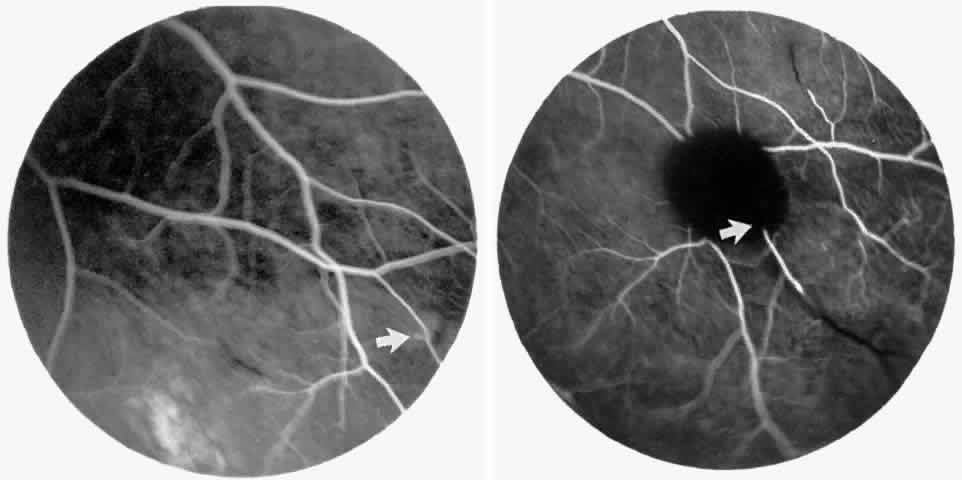

The occluded arterioles may be invisible or may have a “silver-wire” or chalk-white appearance, as first described by Goodman and colleagues39 (Fig. 21). Fluorescein angiography may demonstrate an abrupt complete occlusion at the interface between peripheral nonperfused and posterior perfused retina. Frequently, this occlusion will take place just distal to a branching vessel, giving the appearance of a freshly pruned rose bush. The nonperfused anterior peripheral retina will have a grayish brown appearance and on fluorescein angiography will appear blurred without clearly defined fundus markings.

STAGE II: PERIPHERAL ARTERIOLAR-VENULAR ANASTOMOSES. Following occlusion of the terminal arterioles, anastomotic channels form to channel the blood from the occluded arteriole to the nearest venules. These anastomoses form at the interface between the perfused and nonperfused retina. Most likely, they are dilated preexisting capillaries rather than new vessels, since they do not leak on fluorescein angiography. The redirection of blood flow is probably due to hydrostatic forces (Figs. 22 and 23).

|

STAGE III: PRERETINAL NEOVASCULARIZATION (PROLIFERATIVE SICKLE RETINOPATHY). “Sea fan”-shaped neovascularization typically develops on the venular side of an arteriolar-venular anastomosis, mimicking the normal development of retinal capillaries (Fig. 24).125 A lowered oxygen tension and angiogenic factors released on the venular side may be the stimulus for neovascular growth.125,126 In most instances, the direction of growth is toward the ora serrata, from the perfused retina toward the nonperfused retina. Presumably, this represents an abortive attempt to revascularize the nonperfused retina, initiated by vasoproliferative factors.